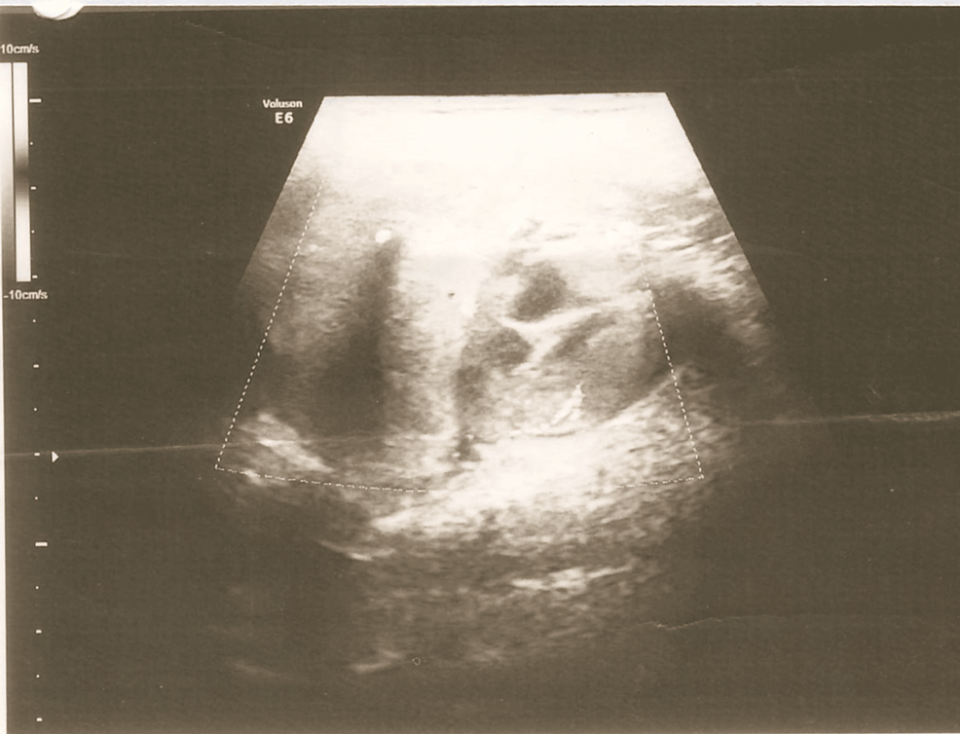

On local examination, there was a single firm mobile swelling in the right submandibular region measuring 5*4 cm and was non-tender. All relevant investigations were done and had normal thyroid function studies. Ultrasonography of the right submandibular region showed an enlarged submandibular gland with a hypoechoic lesion and vascularity on Doppler, suggestive of submandibular sialadenitis (Figure 1). FNAC of the swelling was done, and it showed numerous small basaloid cells in singles and multilayered. These cells have round to regular/oval nuclei with bland, granular chromatin. The background shows a few naked nuclei with fibrous scanty chondromyxoid stroma and hyaline material. These features are suggestive of a basaloid neoplasm like basal cell adenoma or pleomorphic adenoma. Contrast-enhanced computed tomography (CECT) of the neck showed a large lobulated mass with irregular margins and cystic areas in the right submandibular region extending up to the midline; post-contrast showed heterogenous enhancement with necrosis and coarse calcific foci within the lesion, suggestive of malignant neoplasm such as adenoid cystic carcinoma with origin from the deep lobe of the submandibular gland (Figure 2). Another small enhancing lesion with coarse calcific foci was seen at the left pharyngeal mucosal space, suggestive of a metastatic lingual lymph node. Also, the thyroid gland was not visualized, and a small oval isodense lesion with homogenous post-contrast enhancement was seen in the left lateral aspect of trachea, in the expected location of thyroid, suggestive of remnant thyroid/congenital hypoplastic thyroid. Thus the patient was advised surgical excision of the swelling.